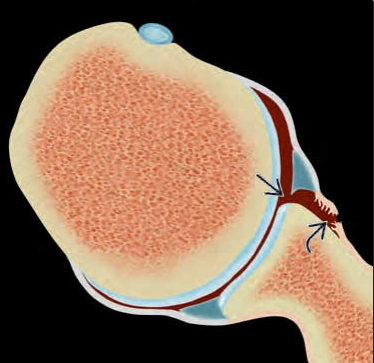

Tổn thương Perthes (Perthes lesion)